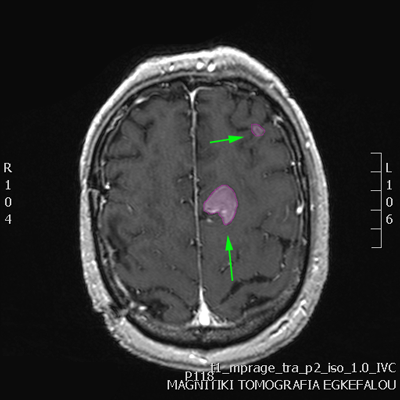

Πολλαπλές μεταστάσεις σε διάφορα σημεία του εγκεφάλου. |